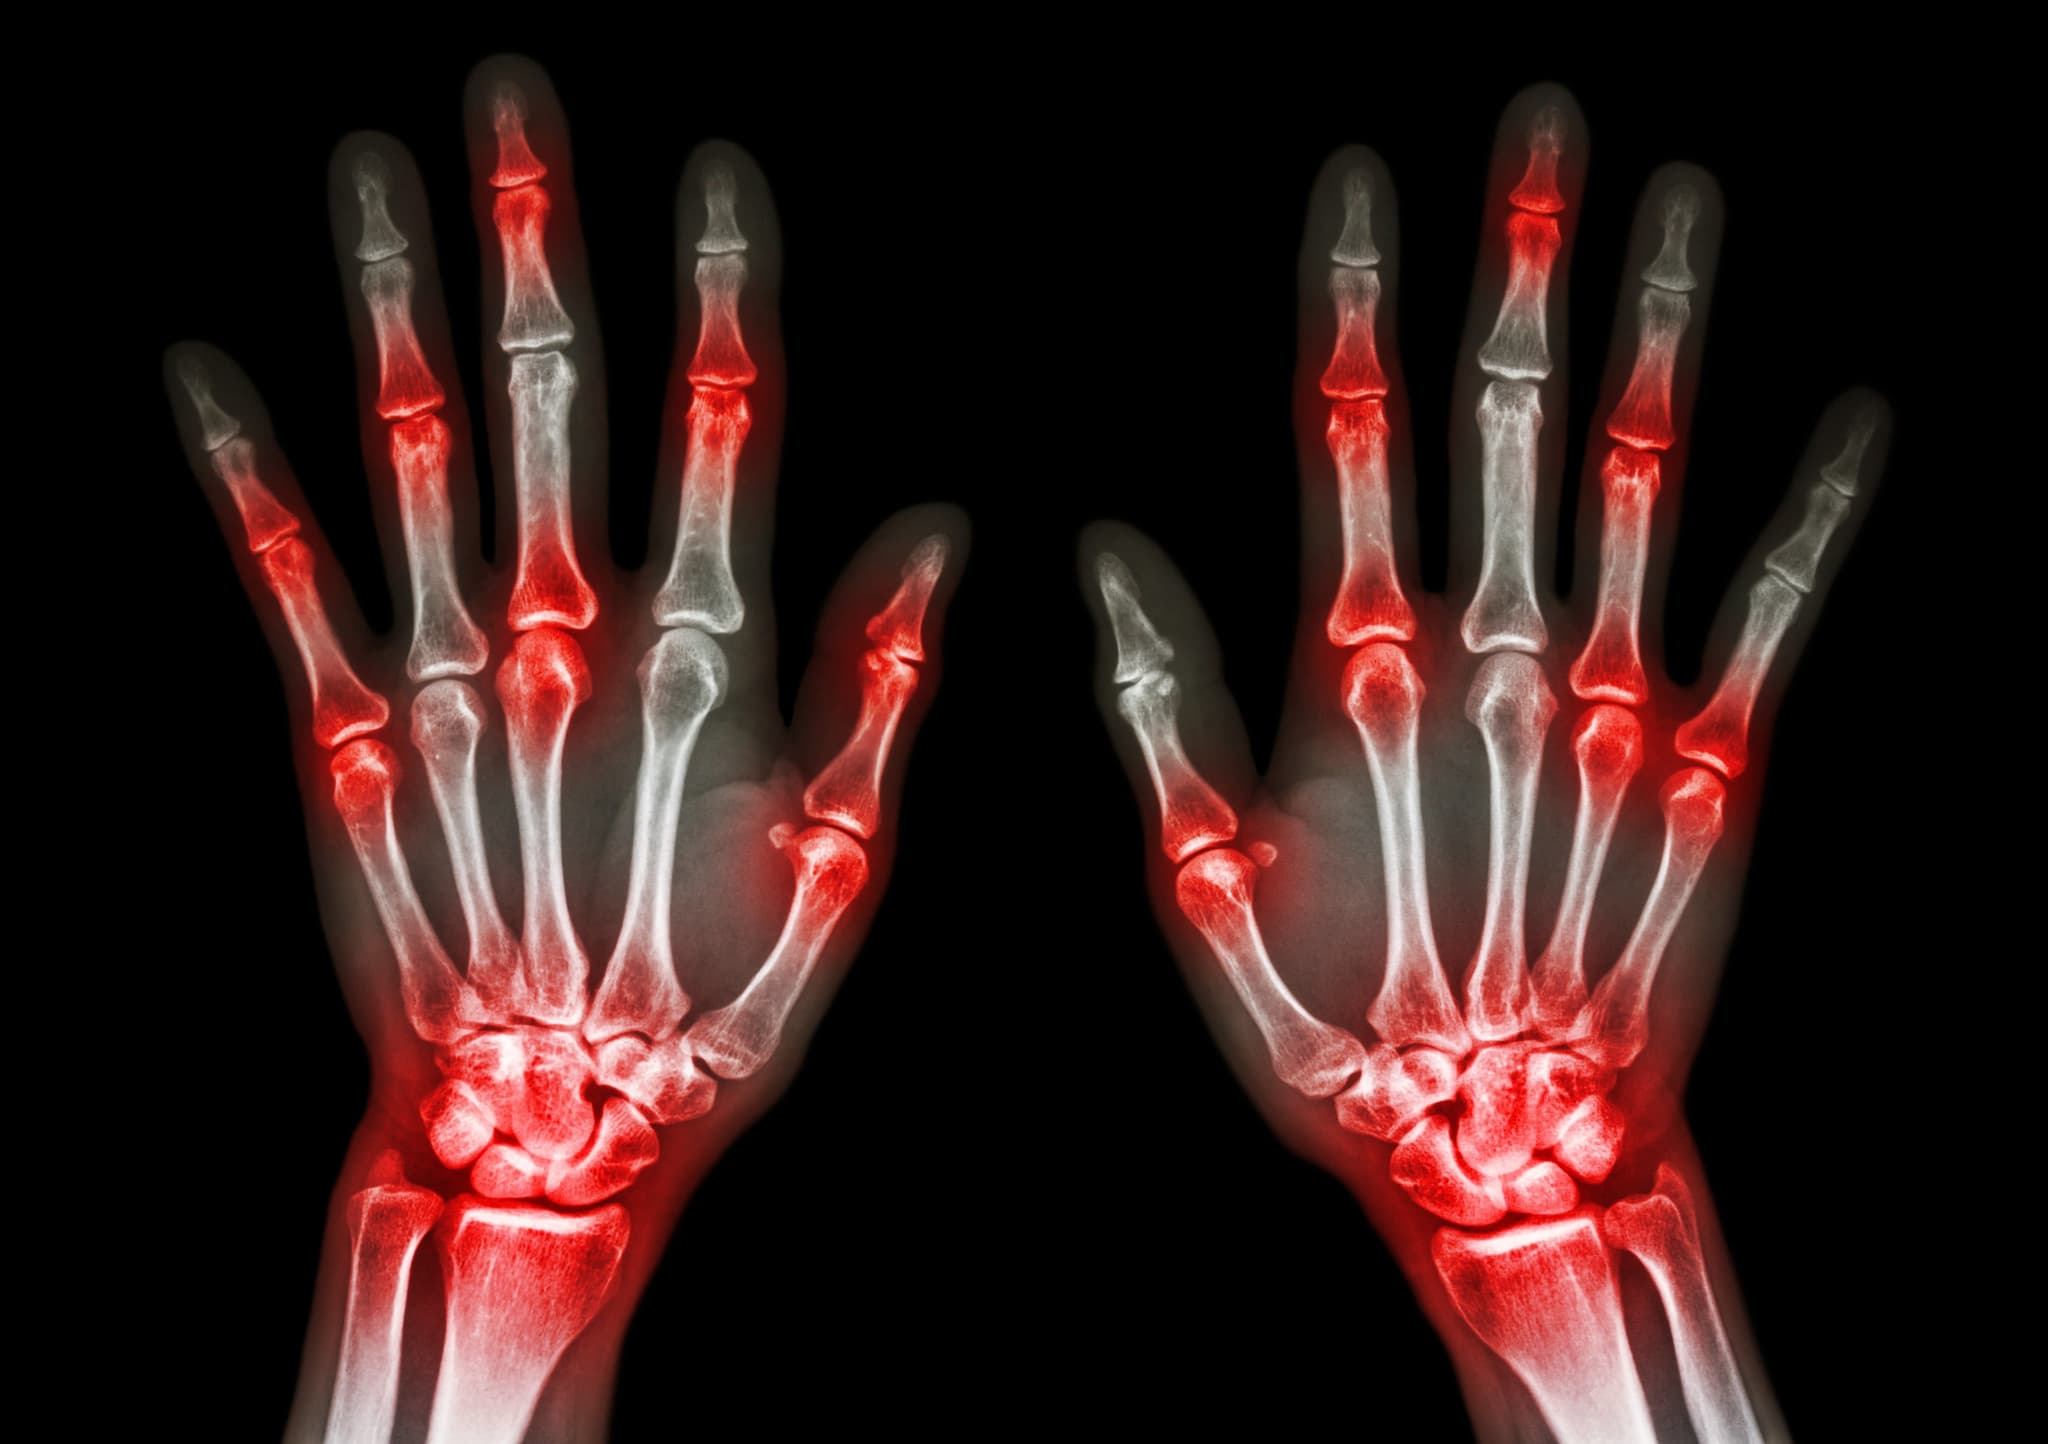

Several parts of the body naturally wear down as we age, especially the joints that help connect our bones. When these joints become inflamed or damaged over time, arthritis can develop.

Arthritis is a progressive condition that tends to get worse over time and is associated with many painful symptoms that can sometimes accompany aging. Some of the more common types are present, to some degree or another, in nearly half of all people by the time they reach age 65.

Symptoms for these types of arthritis, and many others, range from general pain and stiffness to swelling, redness and a reduction of mobility.